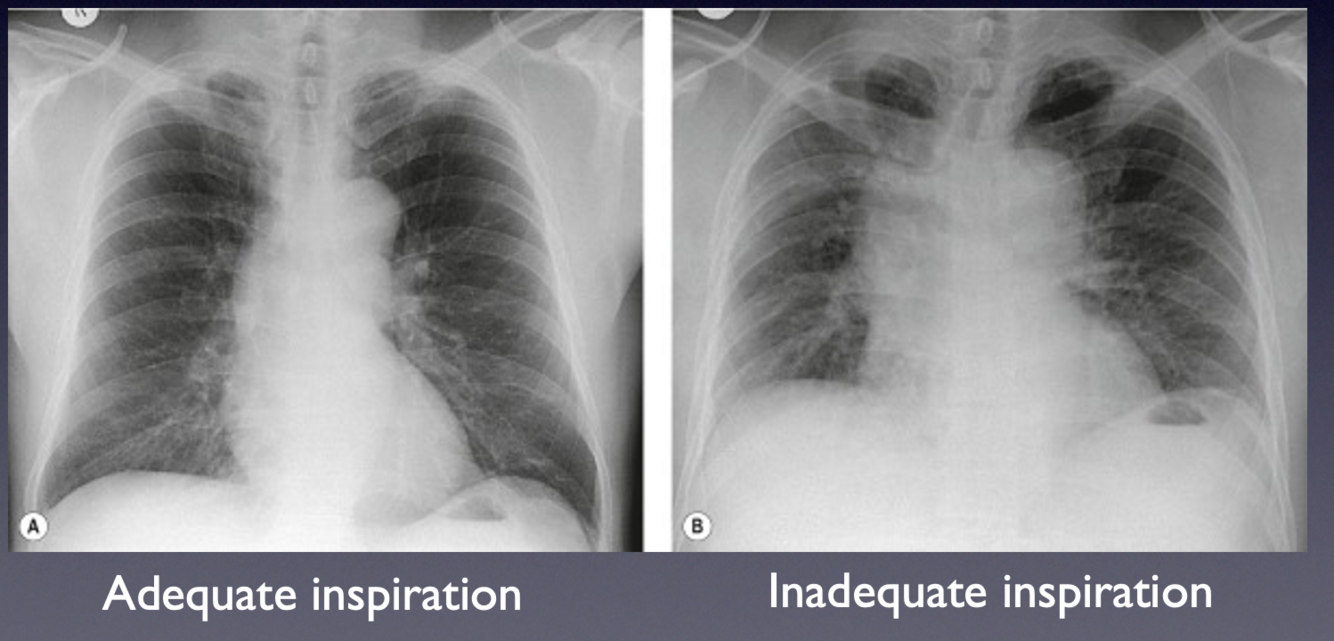

How can a properly inspirated CXR be identified ?

Anterior ends of at least 5 ribs should be visible (see next slide)

-Poorly inspired can simulate pathology when there is none